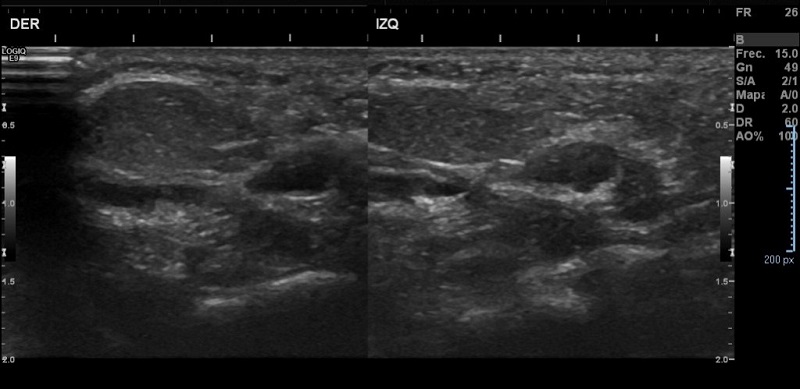

Ante la sospecha de HFPC, se solicita ecografía, que objetiva dos imágenes hipoecogénicas contiguas en cada pie de 23 x 6 mm y 9 x 5 mm, con márgenes imprecisos, con ecoestructura similar a la grasa subcutánea adyacente y escasamente vascularizados, sin evidenciarse extensión a planos profundos, siendo esta descripción compatible con el diagnóstico de sospecha (Figura 3). Posteriormente, es valorado por el Servicio de Dermatología Pediátrica, donde se confirma el diagnóstico.

Figura 3. Lesiones hipoecoicas en cada pie, con ecoestructura similar a la grasa cutánea subyacente